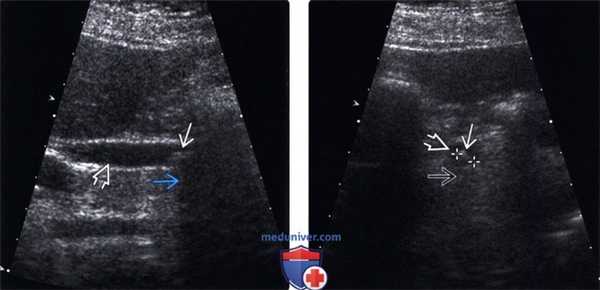

(Левый) На продольном УЗ срезе в общем желчном протоке определяется единичный эхо-генный очаг, отбрасывающий плотную акустическую тень, что соответствует картине конкремента. Общий желчный проток слегка расширен, вероятно, вследствие вызванной конкрементом обструкции.

(Правый) На поперечном косом УЗ срезе у этого же пациента подтверждается наличие конкремента в просвете общего желчного протока. Позади конкремента видна акустическая тень.

(Левый) У того же пациента на продольном УЗ срезе в просвете желчного пузыря определяется несколько конкрементов. Эхо-генные конкременты отбрасывают акустическую тень.

(Правый) При рентгеноскопии при эндоскопической ретроградной холанги-опанкреатографии возле дистального конца расширенного общего желчного протока определяется дефект заполнения, что соответствует картине холедохолитиаза. Также произошел рефлюкс контраста в желчный пузырь, где как дефекты заполнения просвета желчного пузыря выявляются множественные конкременты.

(Левый) На продольном УЗ срезе в общем желчном протоке определяется гиперэхогенный конкремент, отбрасывающий плотную тень. В просвете желчного пузыря определяются другие конкременты.

(Правый) В общем желчном протоке определяются несколько конкрементов, вызывающих небольшое расширение внепеченочных желчных протоков. Цветовая допплерография помогает дифференцировать общий желчный проток (в котором отсутствует цветовая индикация) от прилегающих сосудов.